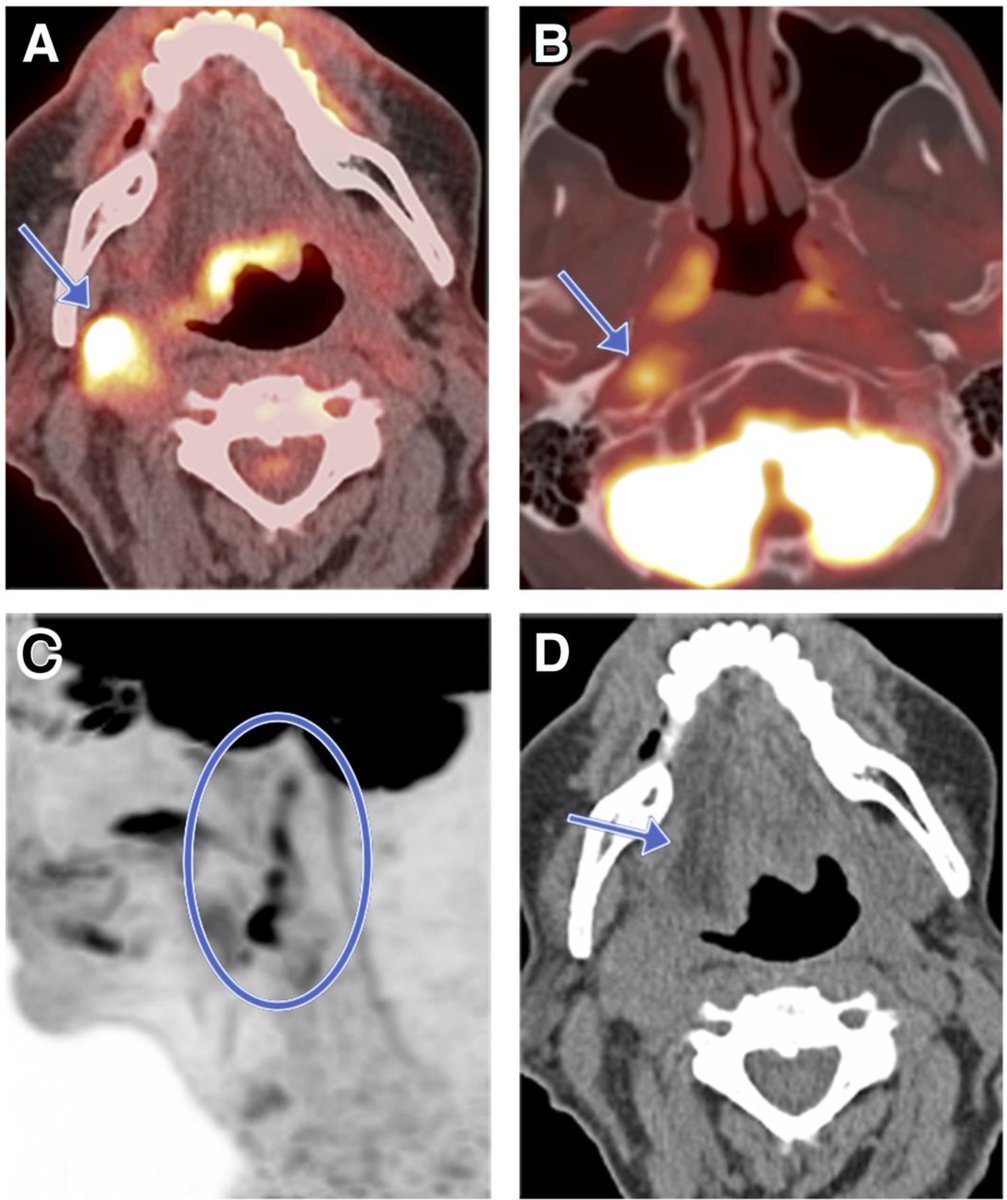

The auriculotemporal nerve is a potential connection between CN V3 and VII for perineural spread. Look just posterior to the mandible!

Normal on the right vs. mucoepidermoid carcinoma from left parotid

Actually, bonus fact: